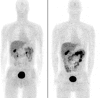

Purpose: The primary purpose of this study was to assess the biodistribution and radiation dose resulting from administration of (18)F-EF5, a lipophilic 2-nitroimidazole hypoxia marker in ten cancer patients. For three of these patients (with glioblastoma) unlabeled EF5 was additionally administered to allow the comparative assessment of (18)F-EF5 tumor uptake with EF5 binding, the latter measured in tumor biopsies by fluorescent anti-EF5 monoclonal antibodies.

Methods: (18)F-EF5 was synthesized by electrophilic addition of (18)F(2) gas, made by deuteron bombardment of a neon/fluorine mixture in a high-pressure gas target, to an allyl precursor in trifluoroacetic acid at 0° then purified and administered by intravenous bolus. Three whole-body images were collected for each of ten patients using an Allegro (Philips) scanner. Gamma counts were determined in blood, drawn during each image, and urine, pooled as a single sample. PET images were analyzed to determine radiotracer uptake in several tissues and the resulting radiation dose calculated using OLINDA software and standard phantom. For three patients, 21 mg/kg unlabeled EF5 was administered after the PET scans, and tissue samples obtained the next day at surgery to determine EF5 binding using immunohistochemistry techniques (IHC).

Results: EF5 distributes evenly throughout soft tissue within minutes of injection. Its concentration in blood over the typical time frame of the study (∼3.5 h) was nearly constant, consistent with a previously determined EF5 plasma half-life of ∼13 h. Elimination was primarily via urine and bile. Radiation exposure from labeled EF5 is similar to other (18)F-labeled imaging agents (e.g., FDG and FMISO). In a de novo glioblastoma multiforme patient, focal uptake of (18)F-EF5 was confirmed by IHC.